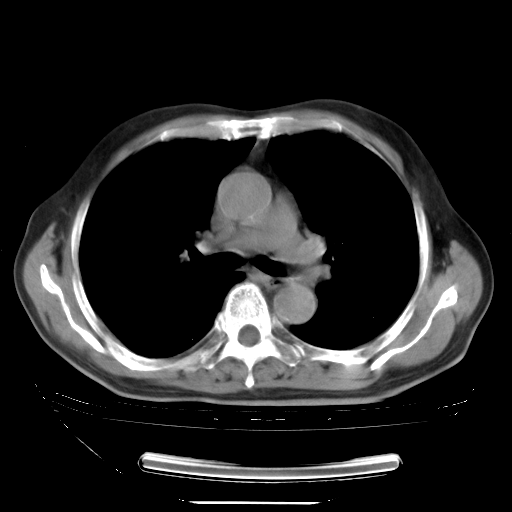

5月9日肺部CT(在4月27日齐鲁医院肺部CT描述部分肺组织磨玻璃样改变,12天后肺组织广泛磨玻璃样改变)

2009年5月9日肺部CT

大致读了系列胸部CT:纵隔窗无明显异常,肺窗:从4、27至今:主要是双肺中下野外带可见毛玻璃样改变,目前处于急性肺泡炎阶段,至于原因考虑1、结替组织或胶原血管性疾病所致?2、恶性疾病如恶组在肺部所致的表现或细支气管肺泡癌?3、药物或其它原因如肺蛋白沉着症所致肺泡炎目前不太可能?总之,明天就去请我院的呼吸科、感染科、血液科和临免专家会诊哈。